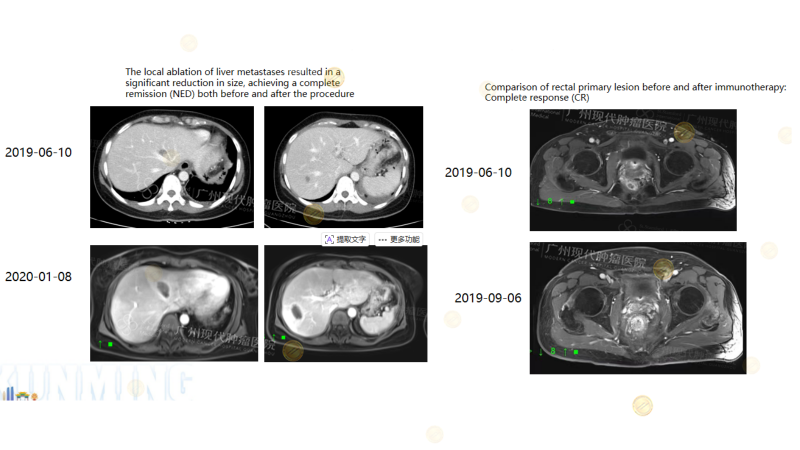

Case1

(Note: 25-year-old male with rectal cancer liver metastasis, MSI-H/KRAS mutation. PD-1 biotherapy achieved CR in the rectal primary lesion; MWA local intervention for liver metastasis aimed for NED.)